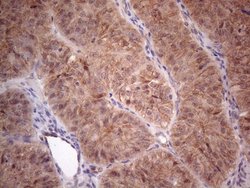

MTF1 Monoclonal Antibody for Western Blot, IHC (P)

| Immunohistochemistry (Paraffin), Western Blot | |